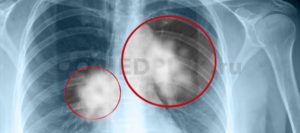

При центральной форме ракового образования, на рентгенографии будет отображаться, что в легких присутствует расширенная сеть сосудов, а также имеются замутненные участки. Когда у легочной онкологии периферический характер, картина на рентгеновском изображении будет отображать присутствие четкой тени с неровными краями, от которой к корню легких отходят отростки в виде лент.

По локализации рак легких подразделяется на центральный, периферический и массивный. Последний встречается достаточно редко. А наиболее распространен центральный.

Как выглядит рак легких на флюорографии? Конечно, опухоль на снимке сложно распознать неспециалисту. Квалифицированный доктор может ее заподозрить по следующим признакам:

- Наличие уплотнения. Чаще всего оно одностороннее, отбрасывает тень. К нему могут примыкать тяжи. При этом заметно, что корни легкого будут несколько расширенными.

- Тень, которую отбрасывает уплотнение, разной формы. Но чаще всего именно шаровидной. Как правило, она имеет нечеткие края, вокруг нее может быть некоторая «лучистость».

При расположении онкообразований в поверхностных слоях органа или же возле места входа главного бронха флюорография выявляет рак в виде темного пятна неясной этиологии.

Если врач-рентгенолог при плановом посещении пациента обнаруживает на снимке такие пятна, он направляет пациента на рентген в двух проекциях или же на компьютерную томографию с целью получить более точные снимки.

Итак, подведем итоги. Можно ли обнаружить рак легких на фото флюорографии? Обнаружить можно, но далеко не в каждом случае. Рак на флюорографии выявляется только при поверхностном расположении очагов поражения.